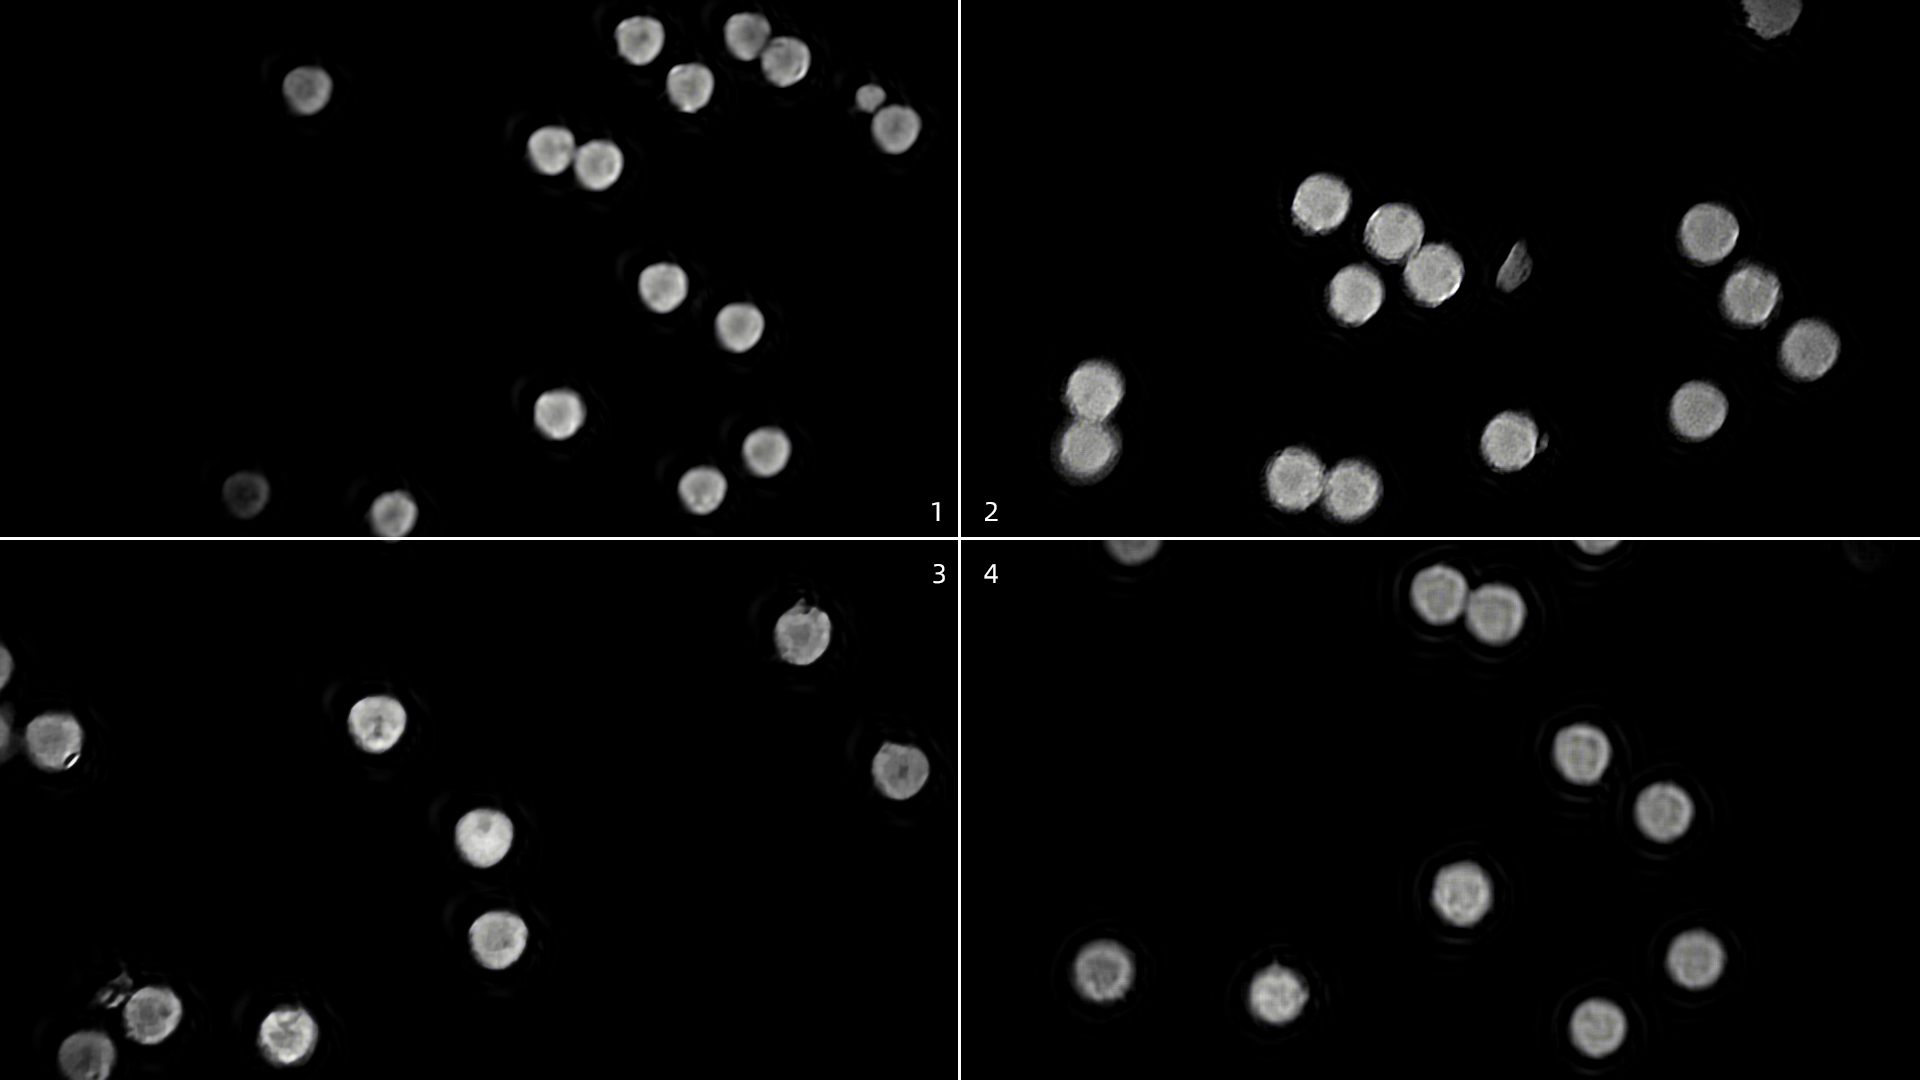

实验数据

本次实验清晰采集到微流控荧光微球的图像数据序列,所采集到的图像清晰、无明显噪声:

实验结论

本实验的成功为进一步研发流式细胞仪细胞核成像检测装置提供了有力支持,验证了将具有高灵敏度、高动态范围、高速、低读出噪声的Gloria 4.2sCMOS相机集成到自组显微镜的微流控成像方案的可行性,且在高动态范围、低噪声特性、成像软件的易用性上的体验优于对标的进口设备。本实验后续将在荧光光路系统上进一步优化,实现产品的标准化、仪器化,以适配流式细胞仪高通量检测的需求,为医学成像设备的选型提供参考。